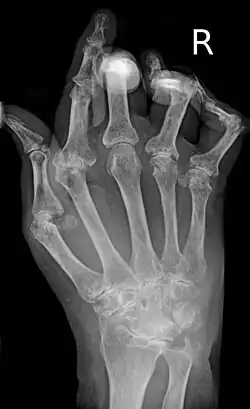

Morphologie der Hand mit cP – die charakteristische Ulnardeviation ist rechts dargestellt.

Der Krankheitsbeginn ist oft schleichend, kann aber auch plötzlich eintreten, mit Schmerzen in den kleinen Finger- oder Zehengelenken. Es können auch andere Gelenke betroffen sein, insbesondere Hand-, Knie-, Schulter, Fuß-, Hüftgelenke. Typischerweise werden bevorzugt die Handwurzelknochen, die Fingergrundgelenke (Metacarpophalangealgelenke) und die Fingermittelgelenke (proximale Interphalangealgelenke, PIP) befallen. Die Fingerend- und Zehenendgelenke (distale Interphalangealgelenke, DIP) sind im Gegensatz zur Psoriasisarthritis nicht betroffen. Die betroffenen Gelenke schwellen an und sind überwärmt. Eine Rötung der betroffenen Gelenke kann hinzukommen. Eine symmetrische (= beidseits auftretende) Synovitis der stammfernen Gelenke ist typisch, aber nicht zwingend. Morgens sind diese Symptome zumeist am stärksten ausgeprägt; es handelt sich dabei um die symptomatische Morgensteife. Im Krankheitsverlauf werden immer mehr Gelenke befallen. Unbehandelt führt sie häufig zur Gelenkzerstörung.

• Bildgebende Verfahren: Zu Beginn und im Verlauf sind Röntgen- oder MRT-Untersuchungen erforderlich, um Schädigungen der Knochen (Erosionen) abschätzen zu können. Typische radiologische Befunde, vor allem im Bereich der Hände, sind gelenknahe Entkalkungen, subchondrale (bzw. gelenknahe[12]) Osteoporose, Destruktionen des umliegenden Knochens, Ankylosen und Gelenkfehlstellungen (Knopflochdeformität, Schwanenhalsdeformität, Ulnardeviation).